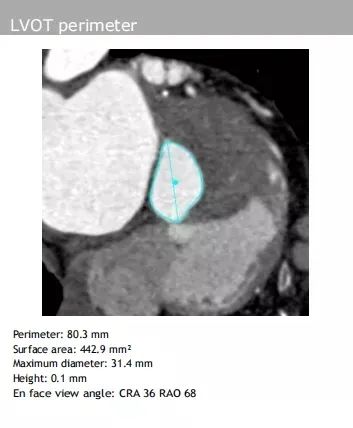

主动脉瓣环:平均直径24.6 mm、周长75.6 mm

左室流出道:最大直径25.5 mm、周长80.3 mm